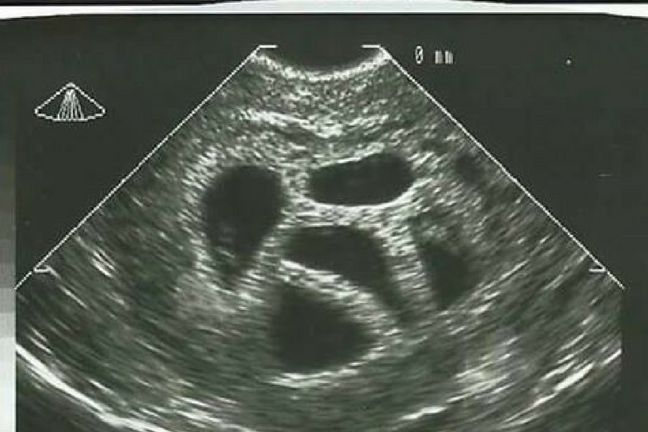

Badanie USG pokazujące pięć zarodków

Badanie USG pokazujące pięć zarodków © Love What Matters, Facebook